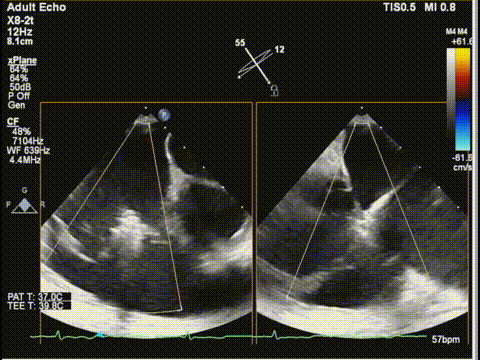

三尖瓣膈叶前叶

三尖瓣膈叶前叶color

三尖瓣胃底界面

三尖瓣胃底界面color